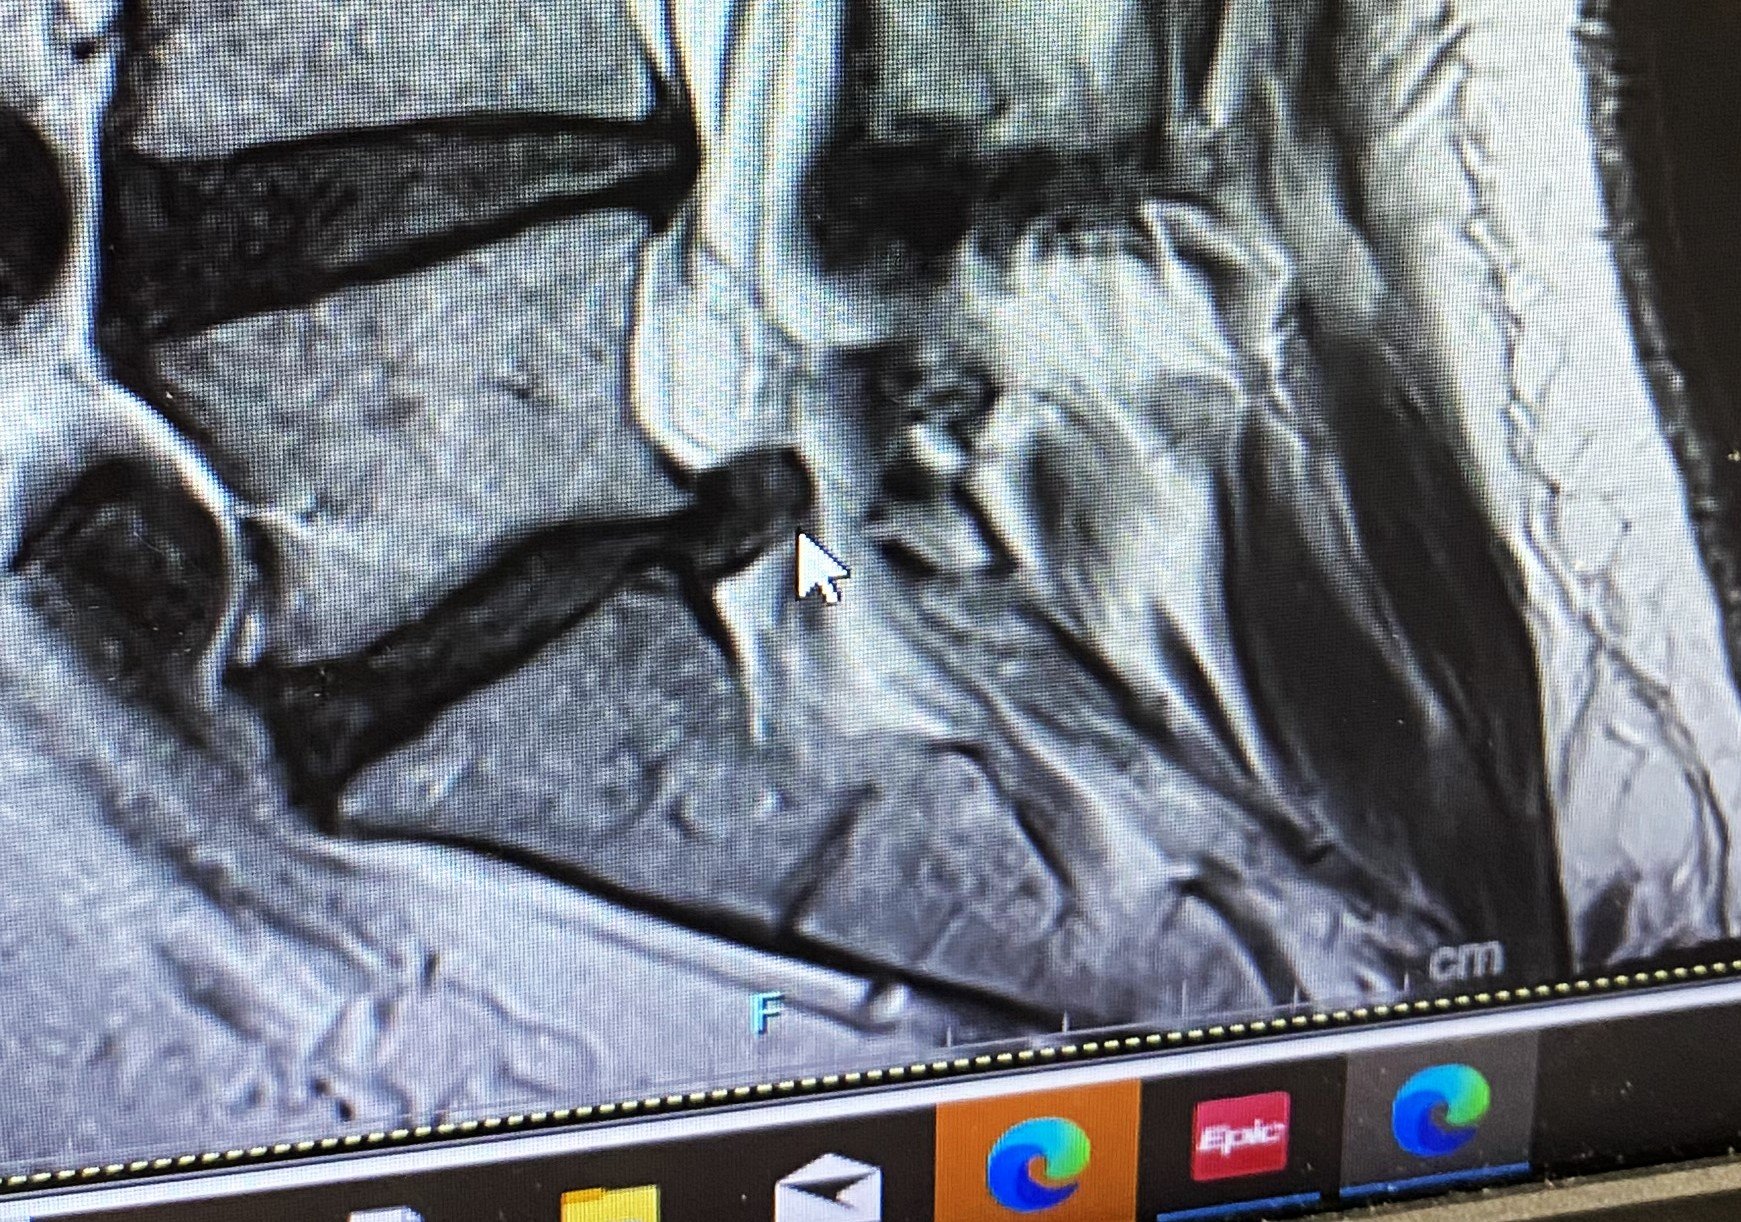

I am counting down the days until I can can get pain relief in the form of discectomy surgery on December 12th. The herniated disc just above my tailbone is the cause of my pain.